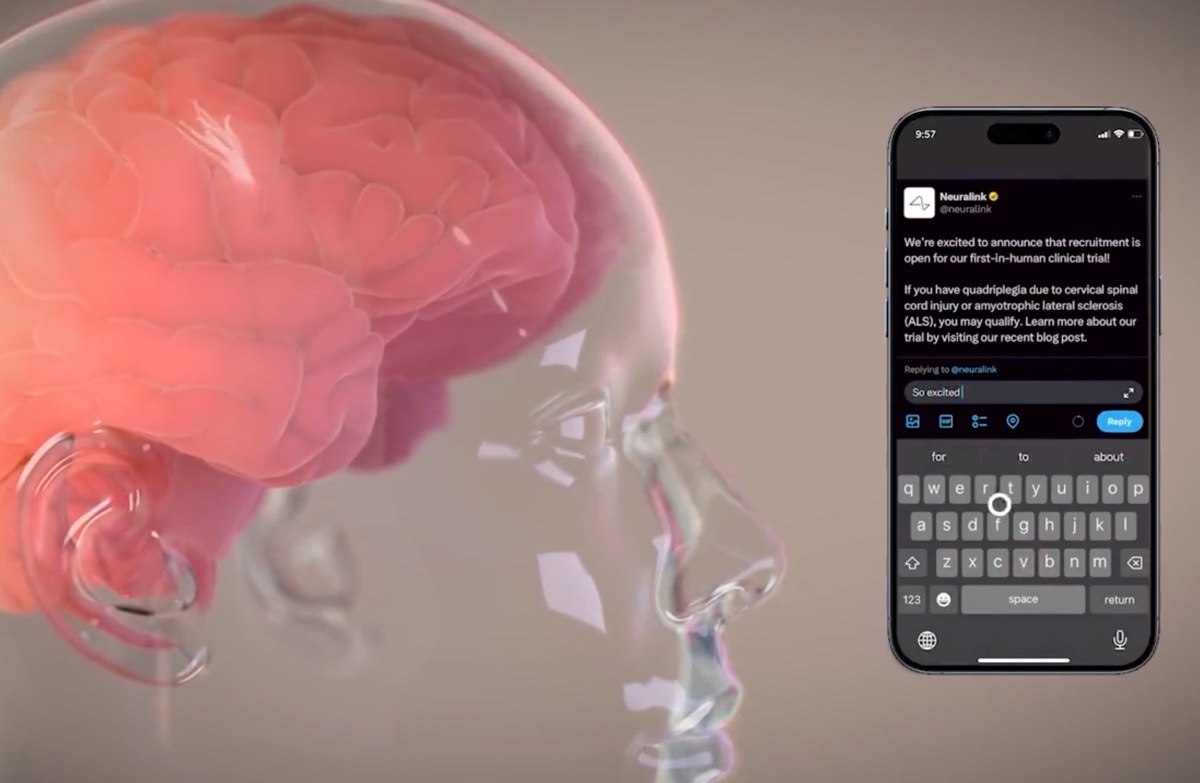

Immagina se Stephen Hawking potesse comunicare più velocemente di un dattilografo o di un banditore d’asta. Questo è l’obiettivo

La startup ha notato alla fine del video che sta cercando volontari che soffrono di quadriplegia a causa di una lesione al midollo spinale, o persone a cui è stata diagnosticata la sclerosi laterale amiotrofica (SLA). Considerando l’annuncio di Musk su X, sembra che Neuralink stia compiendo alcuni passi verso la commercializzazione dei suoi impianti cerebrali.

Check out our latest video to learn more about our PRIME Study! 🧠📱 pic.twitter.com/7zTMFzdZsF

— Neuralink (@neuralink) November 22, 2023